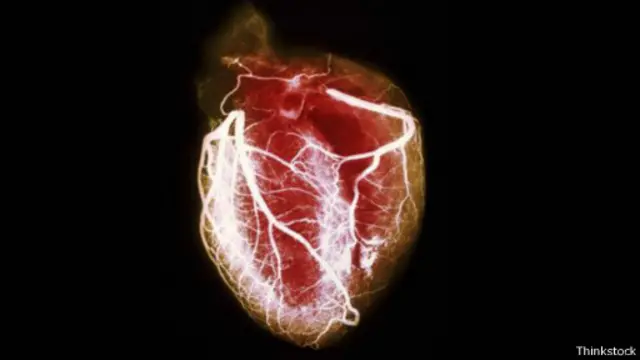

人是否會因為傷心而死?

1986年,一位44歲的女士被送到馬薩諸塞綜合醫院。她一整天都感覺良好,但下午卻突然覺得極度胸悶,疼痛感甚至放射到左臂。這是典型的心臟病發作症狀,但令人不解的是,她並未患有冠狀動脈性心臟病。她心臟周圍的血管裏也沒有危及生命的血栓。

表面看來像是心臟病發作,但其實不是。托馬斯·瑞恩(Thomas Ryan)和約翰·法倫(John Fallon)在《新英格蘭醫學期刊》(New England Journal of Medicine)上介紹了這個罕見病例。他們表示,這位病人的心肌明顯受損,但這卻是由情緒引起的,而非生理原因導致的。當天早些時候,這位女士剛剛得知她17歲的兒子自殺身亡。